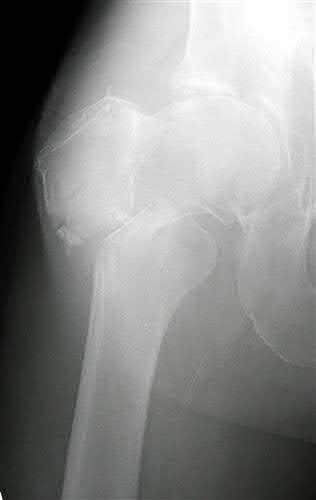

Question 8

A 13-year-old boy with a BMI in the 95th percentile presents with a 2-month history of vague left knee and thigh pain. On physical examination, he has an obligate external rotation of the left hip with passive hip flexion. Radiographs confirm a slipped capital femoral epiphysis (SCFE). Which of the following best describes the anatomic displacement of the femoral metaphysis relative to the epiphysis in this condition?

Explanation

In Slipped Capital Femoral Epiphysis (SCFE), the proximal femoral epiphysis remains relatively secure in the acetabulum while the femoral neck (metaphysis) displaces. Because the mechanical axis of weight-bearing forces acts anteriorly and superiorly on the proximal femur, the metaphysis translates anteriorly and superiorly. Clinically and radiographically, this makes the epiphysis appear to have slipped posteriorly and inferiorly relative to the neck. Therefore, the metaphysis moves anteriorly and superiorly.